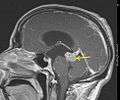

Low grade astrocytoma of the midbrain (lamina tecti). Sagittal T1-weighted magnetic resonance imaging after contrast medium administration. The tumor is marked with an arrow. The CSF spaces in front of the tumor are expanded due to compression-induced hydrocephalus internus.